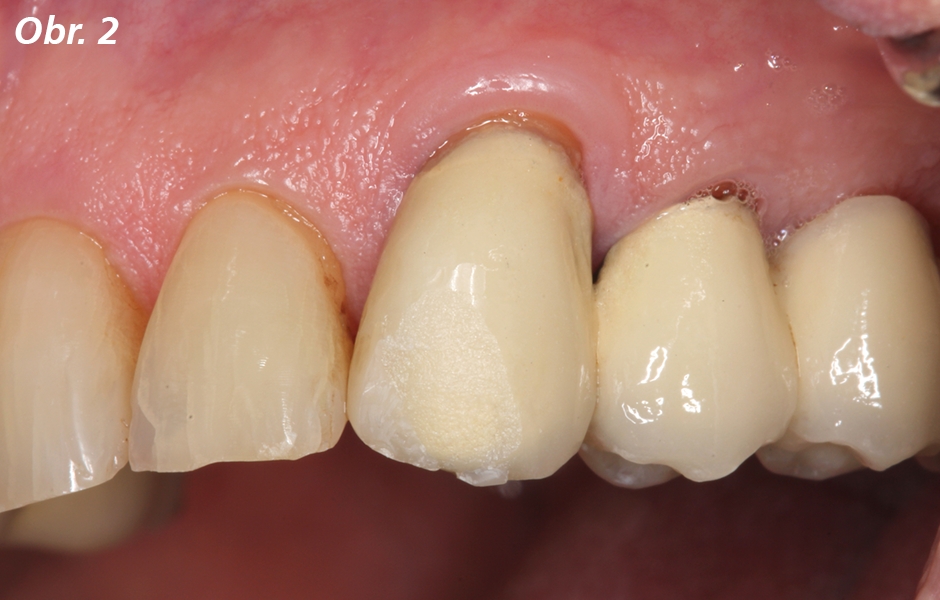

Pacient s metalokeramickými korunkami se dostavil s meziálně- incizálním odlomením keramiky na zubu 23 (obr. 1, 2). Korunky byly nasazeny předchozím zubním lékařem. Pacient chtěl precizně rekonstruovat tvar korunek, použité materiály nebyly známy. Pacient měl problém hlavně s estetikou a hrubostí povrchu odlomené keramiky. Klinické vyšetření odhalilo věku odpovídající zuby s protetickými a přímými konzervativními rekonstrukcemi. Byly zjištěny všeobecně mírné gingivální recesy, výraznější v oblasti špičáků. Orální hygiena byla dobrá, okraj korunky zubu 23 byl obnažen, ale nevykazoval žádné klinické abnormality (obr. 2). Ani korunka ani okraj korunky v současném stavu nebyly důvodem pro výměnu celé korunky. Během konzultace s pacientem proto bylo rozhodnuto ve prospěch přímé, intraorální opravy pomocí nanohybridního kompozita Charisma Diamond. Odlomení keramiky na zubu 23 patřilo mezi tzv. jednoduchá odlomení, což znamená, že povrch lomu je celý v keramice, bez obnažení kovové konstrukce. Po vyleštění opravovaného zubu byl nasazen kofferdam a okraje poškozeného keramického povrchu byly pomocí jemného diamantu rozšířeny o zhruba 1 mm nad okraje lomu. Poté byl celý opravovaný povrch zdrsněn karbidkřemičitým kaménkem, důkladně opláchnut vodní sprchou a osušen. Nyní bylo možné opracovaný keramický povrch snadno odlišit od ostatních částí (obr. 3). Alternativně je také možné povrch intraorálně opískovat oxidem hlinitým, přičemž je třeba chránit měkké tkáně. Předchozí rizikové intraorální ošetření povrchu silikátové keramiky kyselinou fluorovodíkovou je vynecháno. Na čistý a suchý povrch preparovaného keramického povrchu se nanese tenká vrstva primeru GLUMA Ceramic Primer (obr. 4).

Detailní pohled na odlomenou oblast na zubu 23. Jedná se o tzv. jednoduché odlomení, při němž je postižena pouze keramika a nedošlo k obnažení kovové konstrukce